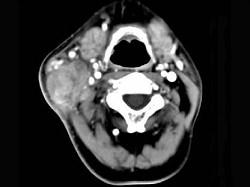

问题 65岁男性,吸烟史30余年,近半年来颈部出现疼痛性肿块,CT扫描如图所示,请选择最可能诊断 ( )

选项 A、淋巴结转移癌 B、软组织脓肿 C、血管瘤 D、神经鞘瘤 E、淋巴结核

答案 A